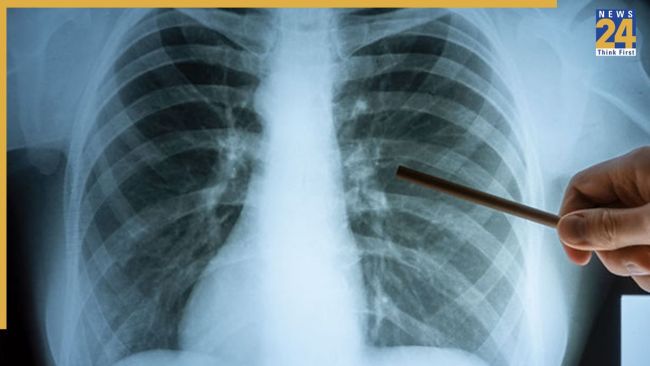

рдЕрд╣рдорджрд╛рдмрд╛рдж рд╢рд╣рд░ рд╕реЗ рд╕реНрд╡рд╛рд╕реНрдереНрдп рдХреЛ рд▓реЗрдХрд░ рд╕рд╛рдордиреЗ рдЖрдИ рдПрдХ рдбрд░рд╛рдиреЗ рд╡рд╛рд▓реА рд░рд┐рдкреЛрд░реНрдЯ .рдЖрдВрдХрдбрд╝реЛрдВ рдХреЗ рдореБрддрд╛рдмрд┐рдХ, рдЕрд╣рдорджрд╛рдмрд╛рдж рдореЗрдВ рдкрд┐рдЫрд▓реЗ рдПрдХ рд╕рд╛рд▓ рдореЗрдВ рдЯреАрдмреА рдпрд╛рдиреА рдЯреНрдпреВрдмрд░рдХреНрд▓реЛрд╕рд┐рд╕ рдХреЗ 15 рд╣рдЬрд╛рд░ рд╕реЗ рдЬрд╝реНрдпрд╛рджрд╛ рдирдП рдорд╛рдорд▓реЗ рджрд░реНрдЬ рдХрд┐рдП рдЧрдП рд╣реИрдВ.

15,461 рдорд░реАрдЬреЛрдВ рдореЗрдВ рд╕реЗ 10,809 рдорд░реАрдЬ рд╕рд░рдХрд╛рд░реА рдЕрд╕реНрдкрддрд╛рд▓реЛрдВ рдореЗрдВ рд╣реИ рдЬрдмрдХрд┐ 4652 рдорд░реАрдЬ рдирд┐рдЬреА рдЕрд╕реНрдкрддрд╛рд▓реЛрдВ рдореЗрдВ рдЗрд▓рд╛рдЬ рдХрд░рд╡рд╛ рд░рд╣реЗ рд╣реИрдВ

рдЗрд╕рд╕реЗ рднреА рдЬрд╝реНрдпрд╛рджрд╛ рдЪрд┐рдВрддрд╛рдЬрдирдХ рдмрд╛рдд рдпрд╣ рд╣реИ рдХрд┐ рдЗрд╕ рджреМрд░рд╛рди 700 рд▓реЛрдЧреЛрдВ рдиреЗ рдЗрд╕ рдмреАрдорд╛рд░реА рд╕реЗ рдЕрдкрдиреА рдЬрд╛рди рдЧрдВрд╡рд╛ рджреА рд╣реИ.""рд╕реНрд╡рд╛рд╕реНрдереНрдп рд╡рд┐рднрд╛рдЧ рдХреА рд░рд┐рдкреЛрд░реНрдЯ рдмрддрд╛рддреА рд╣реИ рдХрд┐ рд╡рдЯрд╡рд╛, рдмрд╣рд░рд╛рдордкреБрд░рд╛ рдФрд░ рдЧреЛрдорддреАрдкреБрд░ рдЬреИрд╕реЗ рдЗрд▓рд╛рдХреЗ рдЯреАрдмреА рдХреЗ рд╕рдмрд╕реЗ рдмрдбрд╝реЗ рд╣реЙрдЯрд╕реНрдкреЙрдЯ рдмрдирдХрд░ рдЙрднрд░реЗ рд╣реИрдВ.

рдПрдХ рд╕рд╛рд▓ рдореЗрдВ рдХреБрд▓ 1,49,710 рд╕рдВрджрд┐рдЧреНрдз рдорд░реАрдЬреЛрдВ рдХреА рдЬрд╛рдВрдЪ рдХреА рдЧрдИ рдереА рдЬрд┐рдирдореЗрдВ рд╕реЗ 15461 рдЯреАрд╡реА рдХреЗ рдорд░реАрдЬ рдкрд╛рдП рдЧрдП.. рдЯреАрдмреА рдорд░реАрдЬреЛрдВ рдХреА рд╣реБрдИ 700 рдореЗрдВ рдореМрдд рдореЗрдВ рд╕реЗ 59 рдлреАрд╕рджреА рдореМрддреЗрдВ рд░реЛрдЧ рдХрд╛ рджреЗрд░реА рд╕реЗ рдкрддрд╛ рдЪрд▓рдиреЗ рдХреЗ рдЪрд▓рддреЗ 30 рджрд┐рди рдХреЗ рднреАрддрд░ рд╣реА рд╣реЛ рдЧрдИ .

рддрд╛рдЬрд╛ рд╕реНрдерд┐рддрд┐ рдХреЗ рдореБрддрд╛рдмрд┐рдХ рд░реЛрдЬрд╛рдирд╛ рдЯреАрдмреА рдХреЗ 42 рдирдП рдорд╛рдорд▓реЗ рдЖ рд░рд╣реЗ рд╣реИрдВ рдФрд░ рдпрд╣ рдЬрд╛рдирд▓реЗрд╡рд╛ рд░реЛрдЧ рд░реЛрдЬ рджреЛ рд▓реЛрдЧреЛрдВ рдХреА рдореМрдд рдХреА рд╡рдЬрд╣ рдмрди рд░рд╣рд╛ рд╣реИ .рд╡рд┐рд╢реЗрд╖рдЬреНрдЮреЛрдВ рдХрд╛ рдорд╛рдирдирд╛ рд╣реИ рдХрд┐ рдХреБрдкреЛрд╖рдг рдФрд░ рдмреАрдорд╛рд░реА рдХрд╛ рджреЗрд░реА рд╕реЗ рдкрддрд╛ рдЪрд▓рдирд╛, рдореМрддреЛрдВ рдХрд╛ рд╕рдмрд╕реЗ рдореБрдЦреНрдп рдХрд╛рд░рдг рдмрди рд░рд╣рд╛ рд╣реИ.

рд╣рд╛рд▓рд╛рдВрдХрд┐ рд╕рд░рдХрд╛рд░ рдкреЛрд╖рдг рдпреЛрдЬрдирд╛ рдХреЗ рддрд╣рдд рдорд░реАрдЬреЛрдВ рдХреЛ рдЖрд░реНрдерд┐рдХ рдФрд░ рдЪрд┐рдХрд┐рддреНрд╕рд╛ рд╕рд╣рд╛рдпрддрд╛ рджреЗ рд░рд╣реА рд╣реИ, рд▓реЗрдХрд┐рди рдореМрдд рдХреЗ рдмрдврд╝рддреЗ рдЖрдВрдХрдбрд╝реЗ рдмрддрд╛рддреЗ рд╣реИрдВ рдХрд┐ рдЕрднреА рдЬрд╛рдЧрд░реВрдХрддрд╛ рдХреА рдФрд░ рднреА рдЬрд╝рд░реВрд░рдд рд╣реИ.